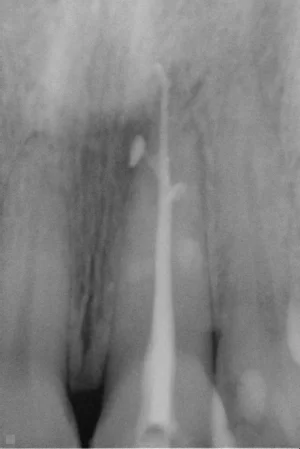

Before

Root canal therapy is required when the dental nerve is damaged. In a healthy tooth, blood vessel, nerve and lymphatic systems are all present inside a hollow tube inside the tooth. When a tooth is diseased, all the dead tissue must be removed, cleaned and sealed. The success of a root canal treatment depends on the perfect hermetic seal of the tooth on both ends.